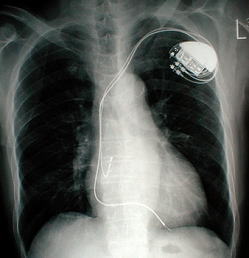

心臓のペースメーカー、人工関節、美容成形の目的で体内に埋め込むシリコン材料等は、いずれもインプラントと呼ばれます。